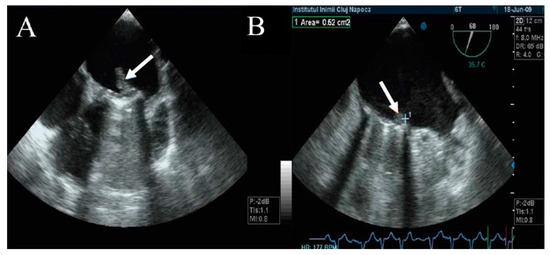

TEE has a major role in describing the size, mobility, and thrombus extension. It also has the ability to describe whether the thrombus is obstructive or nonobstructive, an essential aspect in the choice of therapeutic management (Figure 5) [1,21,22,25,27,28,29,30,31,32].

Figure 5.

TEE. Obstructive thrombus on the atrial side of mechanical mitral prosthesis (arrow).

The thrombus can be viewed as a polylobulated, amorphous mass with an echo density equal to the myocardium, an irregular contour, and variable movement that restricts the mobility of the prosthetic discs (Figure 6). The thrombus size defines the severity of the prosthesis obstruction. Generally, a recent onset of symptomatology with hypermobile obstructive thrombi is associated with hemodynamic instability and high embolic risk [21,22,23,24]. Tong et al. reported that a thrombus on left heart prosthesis with an area below 0.8 cm2 is associated with a lower risk of death, as well as embolic events after thrombolytic treatment [34].

Moreover, Ozkan M. et al. reported that a thrombus area above 0.9 cm2 that generates obstruction of the left heart prostheses increases the risk of embolism or death associated with a thrombolytic treatment. Based on this, the 2014 ACC/AHA guideline recommends emergency surgical treatment when the size of the thrombus on the left heart prosthesis is over 0.8 cm2. Thrombolytic treatment is recommended when the size of the thrombus is below 0.8 cm2, with a recent onset of symptoms and NYHA class I–II [10].

The embolic risk depends not only on the thrombus area, but also on the mobility and echogenicity of the thrombus. A recent onset of symptomatology and hypermobile thrombi with reduced echogenicity have a higher embolic risk than those that are hyperechogenic with reduced mobility (Figure 7) [35]. Moving images of floating thrombi on mitral prostheses are illustrated in Video S3 (Supplementary Material).